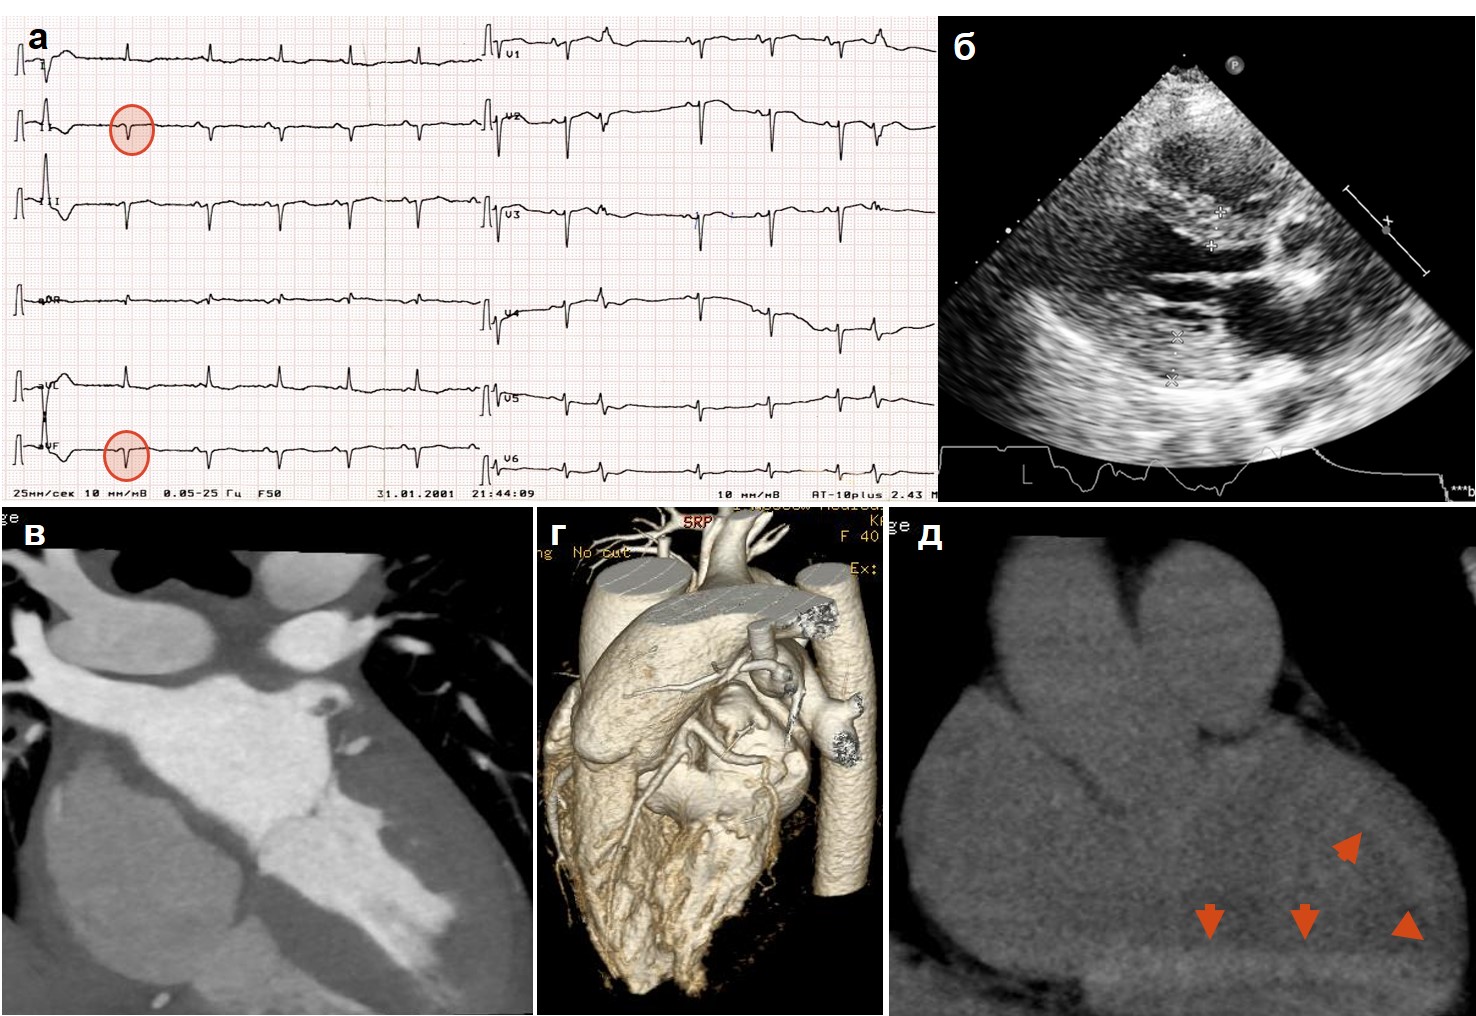

Material and methods. Five 40-79-year old patients with various morphofunctional variants of heart involvement and typical ECG signs (low QRS voltage, QS, non-sufficient R increase, absence of left ventricle (LV) hypertrophy signs) to verify the suspected amyloidosis, underwent EchoCG, immunohistochemistry of blood and urine for light chains of immunoglobulines, biopsy of subcutaneous fat and mucose of the gum/gut; MDCT of the heart (n=3), MRI (n=1), scintigraphy with 99Tc-pyrophosphate with assessment in 1 hour after indicator injection (n=1), endomyocardial biopsy (n=2), titer of anticardial antibodies assessment (n=2), DNA-diagnostics (n=1).

Results. The diagnosis of amyloidosis was confirmed in all cases. Its morpho-functional types were RSMP with LV hypertrophy, hypertrophic cardiomyopathy (HCMP) with no restriction but progressing fall of ejection fraction (EF), dilation cardiomyopathy (DCMP), severe hypertrophy with low EF, minimal hypertrophy with no restriction and systolic dysfunction. There was AL-type diagnosed (n=2, one case with myopathy mimicking “dermatomyositis”), mutant TTR (n=1, novel mutation Thr40Asn) and wild TTR (n=2) types. The leading clinical signs were biventricular heart failure and atrial rhythm disorders: sustained atrial fibrillation in 3 patients (in one, before amyloidosis verification, the RF-modification was done as “labyrinth” surgery, isthmus block with no established efficacy) and frequent supraventricular extrasystoly in one another. To the patient with mutant ATTR the ICD was implanted with further replacement by CRT-D, and increase of EF from 24% to 31% was achieved (patient is followed-up for 8 years). As the morphological equivalent of severe systolic dysfunction in this patient the amyloid deposition in myocardial arteries could be suspected. MDCT revealed typical subendocardial delayed deposition in 2 from 3 patients, in one case there was also diffuse deposition of 99Tc-pyrophosphate in myocardium. Antibodies to the nuclei of cardiomyocytes (specific ANF) was found in a female patient with AL-type and DCMP, which made not to rule out myocarditis.

Conclusion. Cardiac amyloidosis might present as any structural and functional variant of cardiomyopathy, including DCMP. The most specific is diffuse hypertrophy with restriction and EF decrease, but with no LV dilation. Early fall of contractility, ischemia symptoms and LV dilation might be the result of amyloid lesion of small arteries. In the presence of any systemic presentations together with “HCMP”, “RCMP”, “DCMP” there must be amyloidosis ruled out. Myocardial scintigraphy with 99Tc-pyrophosphate is a method of use for the diagnosis of ATTR; MDCT of the heart — for any type of amyloidosis. Cardiac amyloidosis might be followed by significant type of the titer of specific ANF (secondary reaction or concomitance with myocarditis?).